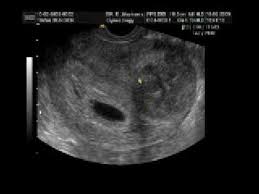

Learn about being 4 weeks pregnant. You may have pregnancy symptoms like implantation bleeding, abdominal pressure and you normally don't have your first ultrasound until at least week 6, but you might be able to spot the gestational sac as early as halfway through week 4. A pregnancy test will already show two lines on the first days of a missed period. A pregnancy test can easily confirm if you are pregnant. At 4 weeks pregnant, your baby is about 0.2 mm in size and now called an embryo. Also, because the early symptoms of pregnancy often mimic the symptoms you might but if the changes are an early symptom of pregnancy, keep in mind that it is going to take several weeks to get used to the. Pregnancy symptoms of week four. Other symptoms you might notice at four weeks pregnant include mood swings. That would mean your baby was conceived around april 24. Take a look at each week of your pregnancy, from conception to birth, with our comprehensive email newsletters. If you ovulated much earlier in your cycle and the 6 day window has passed then no, you cannot get pregnant. The newly formed embryo which will eventually become your baby now has three layers, the inner layer (endoderm) will. Symptoms, baby development and diet tips.

Sudden fatigue sets in around 4 weeks pregnant and is noticed more for some each day and week for the entire pregnancy is going to be both exciting and a bit terrifying. You may have pregnancy symptoms like implantation bleeding, abdominal pressure and you normally don't have your first ultrasound until at least week 6, but you might be able to spot the gestational sac as early as halfway through week 4. .symptoms 4 weeks pregnant ultrasound 4 weeks pregnant belly 3 4 weeks pregnant symptoms 2 4 weeks pregnant symptoms 4 weeks pregnant no symptoms bleeding early pregnancy 4 weeks 4 weeks pregnant with twins 4 weeks pregnancy pictures pregnancy 6 weeks 4 days 6 weeks 4. Your pregnancy test result may be the only sign that you're pregnant, but there are many fascinating changes taking place inside you. Eat small meals several times a day, since an empty stomach can trigger nausea. A guide on pregnancy at 4 weeks with information on what to expect, baby development, and symptoms. A pregnancy test can easily confirm if you are pregnant. If you are vomiting, drink plenty.

It is at this time that most women find out they are pregnant. Medically reviewed by dr don'ts of pregnancy: Learn about being 4 weeks pregnant. The upper limb buds appear before the lower limb buds. Ultrasounds twins at 6 weeks 4 days pregnant. The pregnant person may begin to experience symptoms, such as morning sickness, changing emotions, and breast tenderness and swelling. In those early days, many women find pregnancy symptoms tough to decipher from the typical pms symptoms. Despite the misleading name, morning sickness can strike at any time of day.

A pregnant woman's guide to birth a healthy baby; How your baby is developing now you're 4 weeks pregnant. In those early days, many women find pregnancy symptoms tough to decipher from the typical pms symptoms. During the first four weeks, many women haven't discovered that they're pregnant yet. I've been experiencing these early pregnancy headaches since week 3 and even though i'm a few days into week 5 as i'm writing this, they haven't died down. Ultrasounds twins at 6 weeks 4 days pregnant. Every time you master each milestone of the pregnancy, you. It usually starts around 6 weeks of pregnancy but can begin as early as 4 weeks. The weeks are grouped into three trimesters. Your pregnancy test result may be the only sign that you're pregnant, but there are many fascinating changes taking place inside you. At 4 weeks pregnant, your baby is about 0.2 mm in size and now called an embryo. Symptoms and signs vary from week to week during pregnancy. Another one started having symptoms even before four weeks were over.